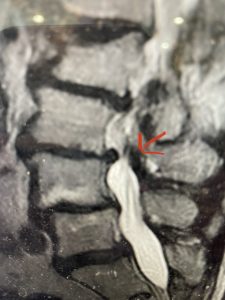

This 57 year-old male had a long history of low back pain and left lower extremity pain and numbness. The patient had failed conservative treatment of physical therapy and epidurals. MRI revealed tight left L2-3 and L3-4 lateral recess stenosis as well as significant right L4-5 facet arthropathy and right lateral recess stenosis as well as a grade 1 L4-5 spondylolisthesis

(Fig 2) Sagittal T2-weighted lumbar MRI demonstrating (arrow) tight lateral recess stenosis

It was felt that the patient should undergo surgical decompression and fusion at L4-5 given his spondylolisthesis. Post operatively he had an uneventful course and he had relief of his leg pain.